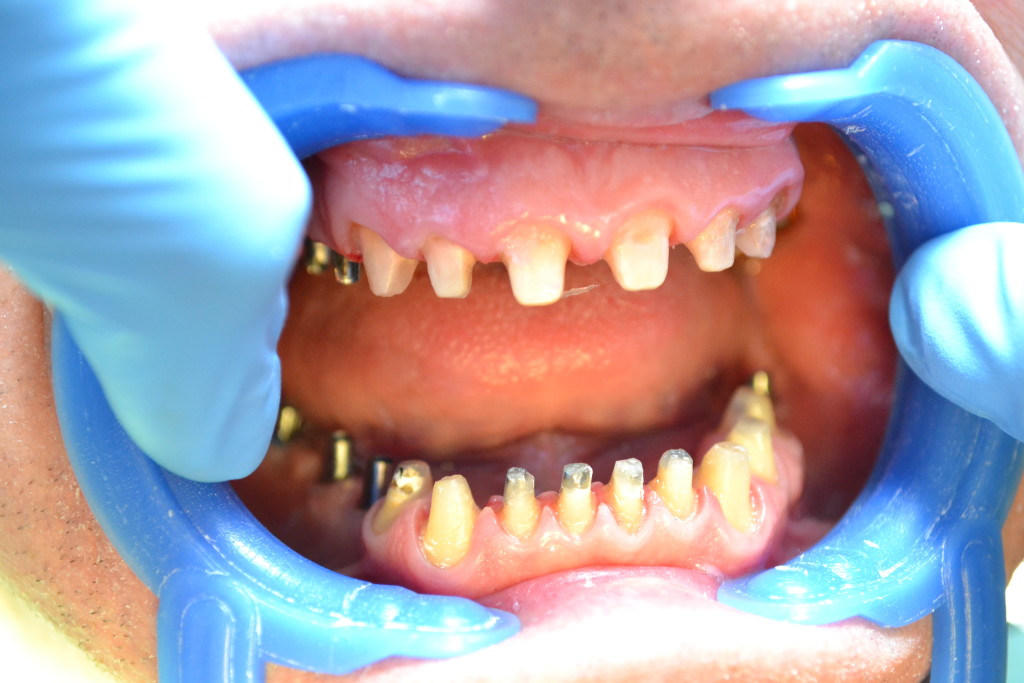

Тотальное протезирование двух челюстей, безметалловые коронки E-max, установленные на вживленные имплантаты Ankylos Dentsply Friadent.

- вживленные имплантаты

- подготовка: препарация + абатменты